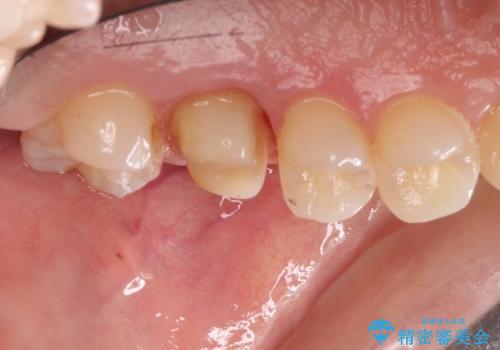

金属の奥歯 → 白い奥歯 根管治療からのやり直し

- 再根管治療→土台の築造 を行った上でのかぶせ物のやり替えをおこないました。

神経の無い歯のかぶせ物をやり替える際は、是非根管治療からしっかりやり直すことをおすすめします。

かぶせ物の種類:Bellezza